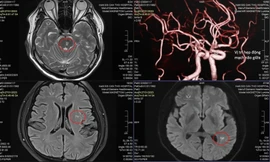

TPO - Đột ngột choáng váng rơi vào hôn mê khi đang bế cháu, tại bệnh viện ông B. được các bác sĩ xác định bị đột quỵ. Người bệnh đã may mắn nhập viện trong “thời gian vàng” sau khi được bác sĩ can thiệp sức khỏe đang bình phục tốt.

TPO - Nam doanh nhân 41 tuổi, đến bệnh viện trong tình trạng tê yếu nửa người do nhồi máu não. Khai thác bệnh sử của bác sĩ từ phía người bệnh ghi nhận, trước đó doanh nhân trẻ thường xuyên tiếp đối tác bằng rượu bia.